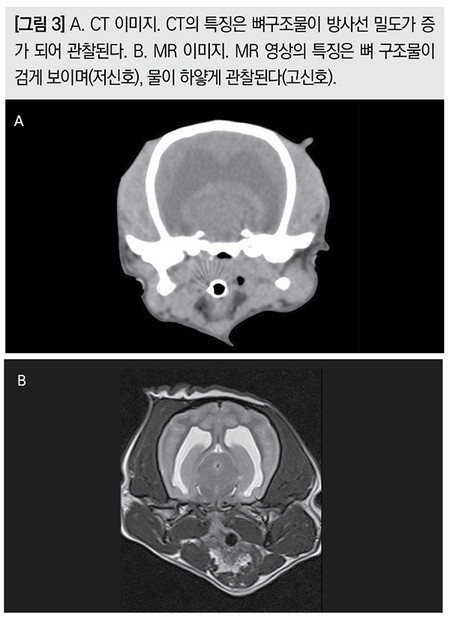

CT는 방사선을 이용한 검사법이며,MR은 강력한 인공자기장을 이용한 검사법이다.두개의 영상을 비교하여 보면 거의 흡사해 동일한 영상으로 착각할 수 있다. 이러한 이유로처음 영상을 접하는 사람은 두개의 영상 차이를 구별하지 못하는 경우도 있다.

CT는 방사선을 이용한 검사법으로 일반 방사선 사진과 판독법이 비슷하고,MR은 자기장을 이용한 검사법으로 영상의 구현을 컴퓨터로 재구성하여 표현하므로 연부 조직을 평가하는 초음파와 비슷하다고 생각하면 된다.

CT는 방사선 선원을 이용하므로 연부조직,공기,뼈를 구별하여 영상을 만들어주며,MR은 연부조직만을 영상화 할 수 있으며,이는 연부조직 내 프로톤(H+)을 이용하여 영상화 하는 방법으로 조직 내에 수소이온을 포함하지 않은 조직은 영상으로 구현할 수가 없다. MR은 오직 연부조직만을 영상으로 표현하게 된다.

CT의 장점은 다양한 각도로 원하는 각도로 단면 영상을 만들 수 있고,정확한 거리를 측정할 수 있는 장점이 있다.MR에서는 확인할 수 없는 골조직의 변화상을 확인할 수 있는 점도 장점이다.